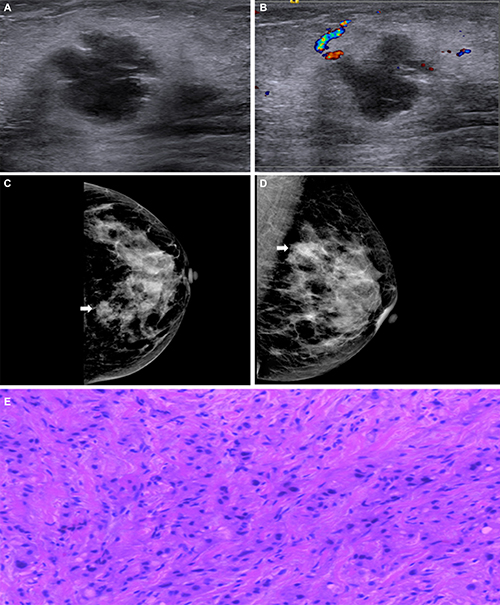

Representative cases are shown in Figure 1 and Figure 2. On the mammogram of the first case, there was a high density mass in the inner upper quadrant of the right breast and its border was spiculated. On ultrasound images we could find an irregular shape mass with circumscribed margin in a low echoic area. The mass size was 3.2 cm × 2.6 cm. The pathological findings confirmed it as invasive ductal carcinoma in nuclear grade 2 with lymphovascular invasion. Immunohistochemical findings were ER negative, PR negative, HER-2 (1+) negative. Because of its CK5/6 and EGFR were both negative, we defined it as NBC. Figure 2 showed an isodensity mass with circumscribed border in the inner upper quadrant of the left Breast. On the ultrasound, there was a mass with lobulated margin in hypoechoic. The mass size was 4.0 cm × 2.3 cm. Its posterior echo wasn’t attenuating and we couldn’t see any calcifications either. Spotty signals could be seen via Color Doppler. The pathological result confirmed invasive ductal carcinoma with a nuclear grade 3. Immunohistochemical findings were ER negative, PR negative, HER-2 (1+) negative. Because of CK5/6 positive, we considered it as BBC.

Figure 2: (A) and (B) Mammography displayed an isodensity mass with circumscribed border in the inner upper quadrant of the left breast (arrows). (C) and (D) Ultrasound revealed a mass with lobulated margin in hypoechoic. The mass size was 4.0 cm × 2.3 cm. Non-accentuating posterior echoes, non-calcification either. No obvious blood signals in the mass. (E) Histopathological image showed it as invasive ductal carcinoma, original magnification, 200×; ER-, PR-, HER2 1+, CK5/6+ and EGFR+ showed it as BBC.